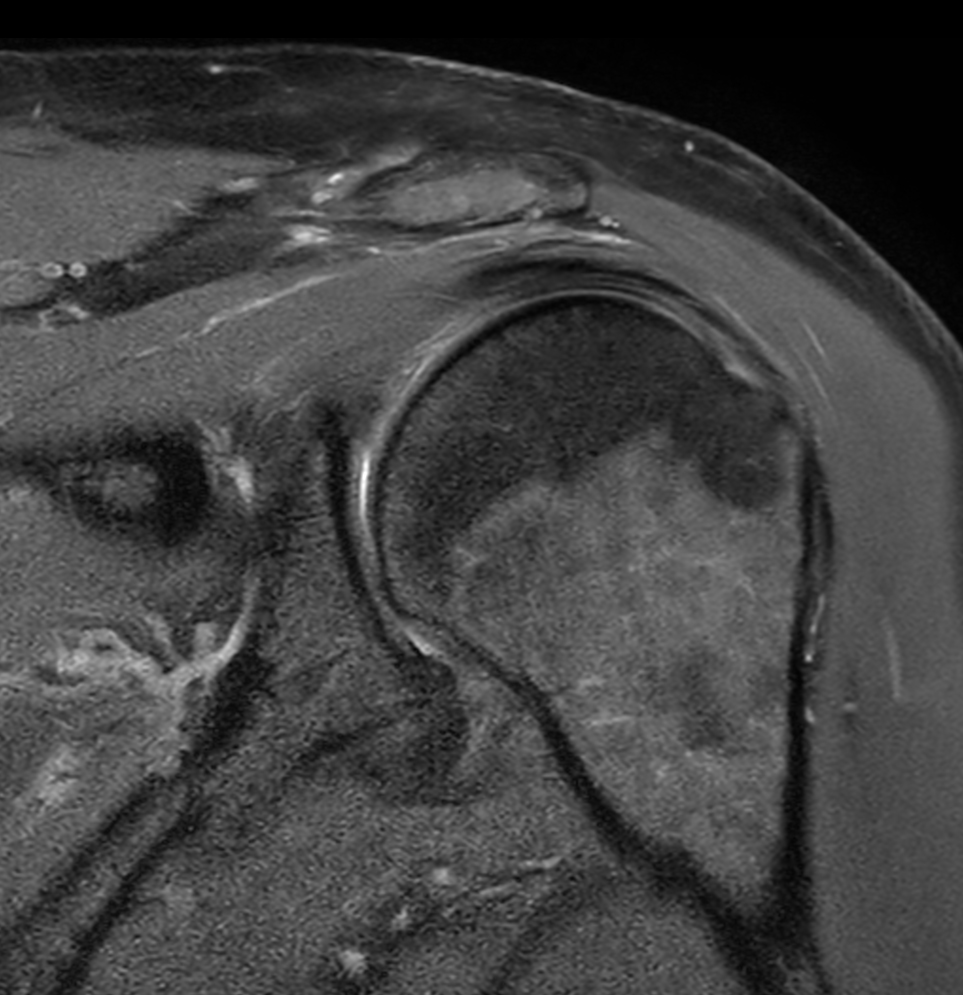

Patient with a shoulder tear

Coronal PDw aTSE mDIXON XD (Water only)

Optimized fat sat sequences for shoulder